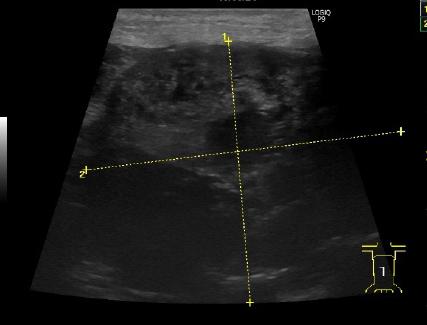

| ケース | 18歳、去勢済男の子のネコちゃん |

| 症状 | 食欲不振と嘔吐で来院されました。血液検査を行ったところ、腎臓の数値の増加が認められました。レントゲン検査ならびにエコー検査において右尿管結石による尿管閉塞が疑われました。 |

| 手術方法 | 尿管閉塞が認められた場合、1,尿管切開による結石摘出術 2,尿管の一部を切除し膀胱と吻合する尿管膀胱吻合術 3、人工尿管を用いた腎臓皮下尿管バイパス手術 4,尿管ステント挿入 5,一時的な腎瘻チューブ設置術などがあります。それぞれの手術方法には一長一短があります。今回はまだ年齢も若く飼い主様のご意向により、尿管切開による結石の摘出を行いました。 |

| 術後経過 | 術後、水腎は解消し腎臓の数値も低下し順調に排尿が認められました。 |

| 図1 | 図2 | 図3 |